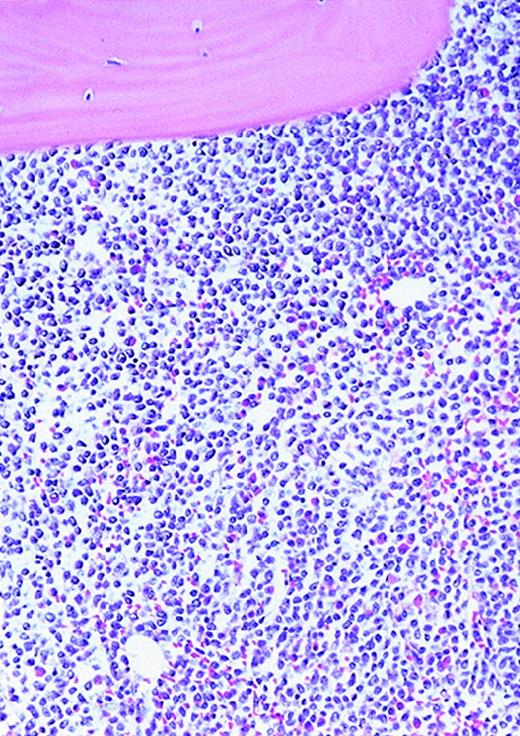

The patients with AML consisted of 8 women and 12 men; the control patients consisted of 12 women and 8 men. The mean age of the AML patients was 59 years (range, 24-87 years). In the control group, the mean age was 49 years (range, 27-71 years). The FAB distribution of the AML cases was as follows: 2 M0, 6 M1, 6 M2, 4 M4, and 2 M7. The cellularity (average ± SEM) was 78% ± 26% (range, 25% to 100%) and 49% ± 8% (range, 35% to 65%) for AML and normal marrows, respectively (P < .0001). Using ULEX-E staining, AML marrows had (average ± SEM) 8.3 ± 3.6 vessels/mm (range, 3.7-19.3) while normal marrows had 4.3 ± 1.8 vessels/mm (range, 1.6-7.9). Using vWF staining of the same specimens, AML marrows had 8.6 ± 3.0 vessels/mm (range, 3.7-15.8) and normal marrows had 4.9 ± 2.2 vessels/mm (range, 1.5-10.1). The differences between the numbers of vessels/mm in AML and normal marrows were highly significant (P < .0001 for both ULEX-E and vWF staining). ULEX-E and vWF exhibited similar staining patterns. Figures1 and 2 show examples of vascularity in normal and AML marrows.

High-power view of vascularity of normal and AML marrow specimens.

Normal or AML bone marrow samples were stained for vWF expression (see Methods). A = 600× view of normal bone marrow showing positive staining in a megakaryocyte as well as 1 vessel. B = 400× view of representative AML marrow showing numerous vessels. Note that some of the vessels are large with irregular and bizarre shapes. C = 600× view of representative AML marrow showing details of vascular endothelial cell staining.